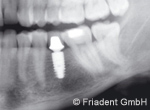

Als Sofortimplantation bezeichnet man die Insertion eines Implantates unmittelbar nach der Zahnentfernung. Dieses Verfahren ist bei bestimmten Voraussetzungen ein erfolgreich durchführbares Behandlungsverfahren. Sind die Weichgewebe und Knochenverhältnisse besonders günstig und bieten dem Implantat eine hohe Stabilität, kann der Zahnersatz direkt eingebracht werden. Dieses Vorgehen bedarf einer besonders sorgfältigen Planung. Häufig ist die Anfertigung einer dreidimensionalen Röntgenaufnahme notwendig.

Die wichtigsten Vorteile der Sofortimplantation sind der Zeitgewinn, das oftmals nicht erforderliche Eröffnen des Zahnfleisches und die daraus resultierende Verringerung von postoperativen Beschwerden wie Schwellung und Wundschmerz. Durch die Einführung der computerunterstützten, navigierten Implantation ist die Genauigkeit der Implantation zusätzlich wesentlich optimiert worden.